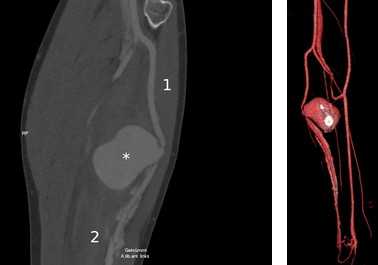

Sonography of the swelling showed a thin-walled anechoic structure of at least 50 mm diameter. Duplex revealed flow inside it and a connection to the anterior tibial artery. The accompanying deep veins showed arterial duplex signals as well. To assess the extent of the injury, a computed tomography (CT) angiography of the lower leg was performed (Figure 2).

Fig. 2. CT angiography scan of the left lower leg: (А) curved resonstruction along the anterior tibial artery, (B) 3D reconstruction: displacement of the artery by the pseudoaneurysm, contrasted deep and superficial veins (images courtesy of Radiologie 360°).

The CT scan confirmed our diagnosis of a pseudoaneurysm of the anterior tibial artery and an arterio-venous fistula. The findings and suggested procedure were carefully discussed with the patient. We carried out an open surgical repair via a vertical skin incision on the lateral side of the lower leg. Intraoperatively, we found the injury to the anterior tibial artery was too extended for a direct repair. Instead, a short vein interposition graft was implanted. For this purpose, a part of the distal greater saphenous vein was explanted at the left ankle. The lesion of the deep vein was treated by primary closure.